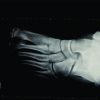

We present a case of a 25-year-old male who presented with complaint of clawing of his left great toe. The patient had sustained a left-sided distal tibia fracture treated with open fixation of the tibia fracture 3 years ago. The implant was removed 18 months after the procedure due to the patient’s preference. After 6 months, the patient initially noticed clawing of his left great toe when he climbed stairs barefoot. He also complained that he had started to find it difficult to sit cross-legged, squat, as well as ride his bicycle due to the tightness he felt in his toes with certain ankle movements on examination, the patient walked with a normal bipedal unassisted gait. He had well-healed surgical scars and a plantigrade foot. Active dorsiflexion of the ankle joint produced an exaggerated flexion of the great toe. With the ankle held in dorsiflexion, it was not possible for the patient to actively or passively fully extend any of the toes (Fig. 1 and 2).

The diagnosis of checkrein deformity of the left great toe was made and attributed to the previous fracture of the distal tibia resulting in scarring or ischemic injury to the toe flexors. The possible patterns of injury could have been an isolated injury to FHL muscle or tendon causing fixed flexion of the great toe. The patient elected for surgical intervention and surgical exploration of FHL tendon at the level of the midfoot was planned. Exploration at the midfoot would give easier access to both tendons free from scar tissue making correction easier. The patient was suitably consented and the exploration was performed under spinal anesthetic with an inflated tourniquet at 250 mmHg. The tendon of FHL was identified (Fig. 3). Subsequent z-plasty of FHL tendon gave a full correction of the great toe flexion contracture (Fig. 4). The patient made an uncomplicated post-operative recovery and after final review, 3 months post-surgery had maintained the full range of movement in all toes (Fig. 5). Weight-bearing photograph is also shown before surgery (Fig. 6) and after surgery (Fig. 7).